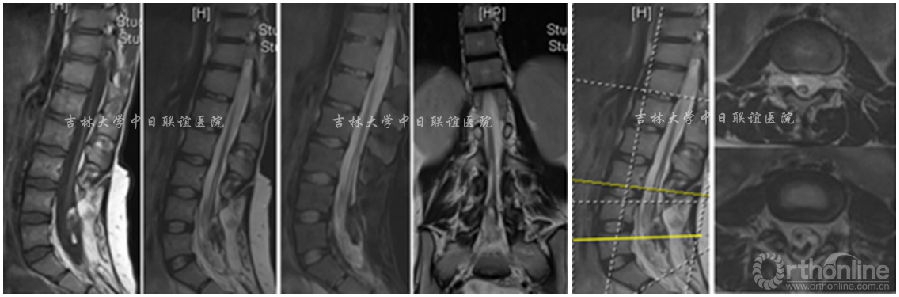

脊柱短缩截骨术后影像学检查:

脊柱短缩截骨术后复查:

术后20天:鞍区、双侧大腿麻木感明显减轻,双侧小腿及双足感觉较术前好转;双侧髂腰肌、股四头肌肌力4级,双侧胫骨前肌3级,踇长伸肌、腓肠肌肌力1级。双侧膝腱及跟腱反射消失,双侧Babinski征(-)。

术后1年:鞍区、双侧大腿仍残留麻木感,双侧小腿及双足感觉较出院时略好转;双侧髂腰肌、股四头肌肌力4级,双侧胫骨前肌3级,踇长伸肌、腓肠肌肌力3级。双侧膝腱及跟腱反射消失,双侧Babinski征(-)。